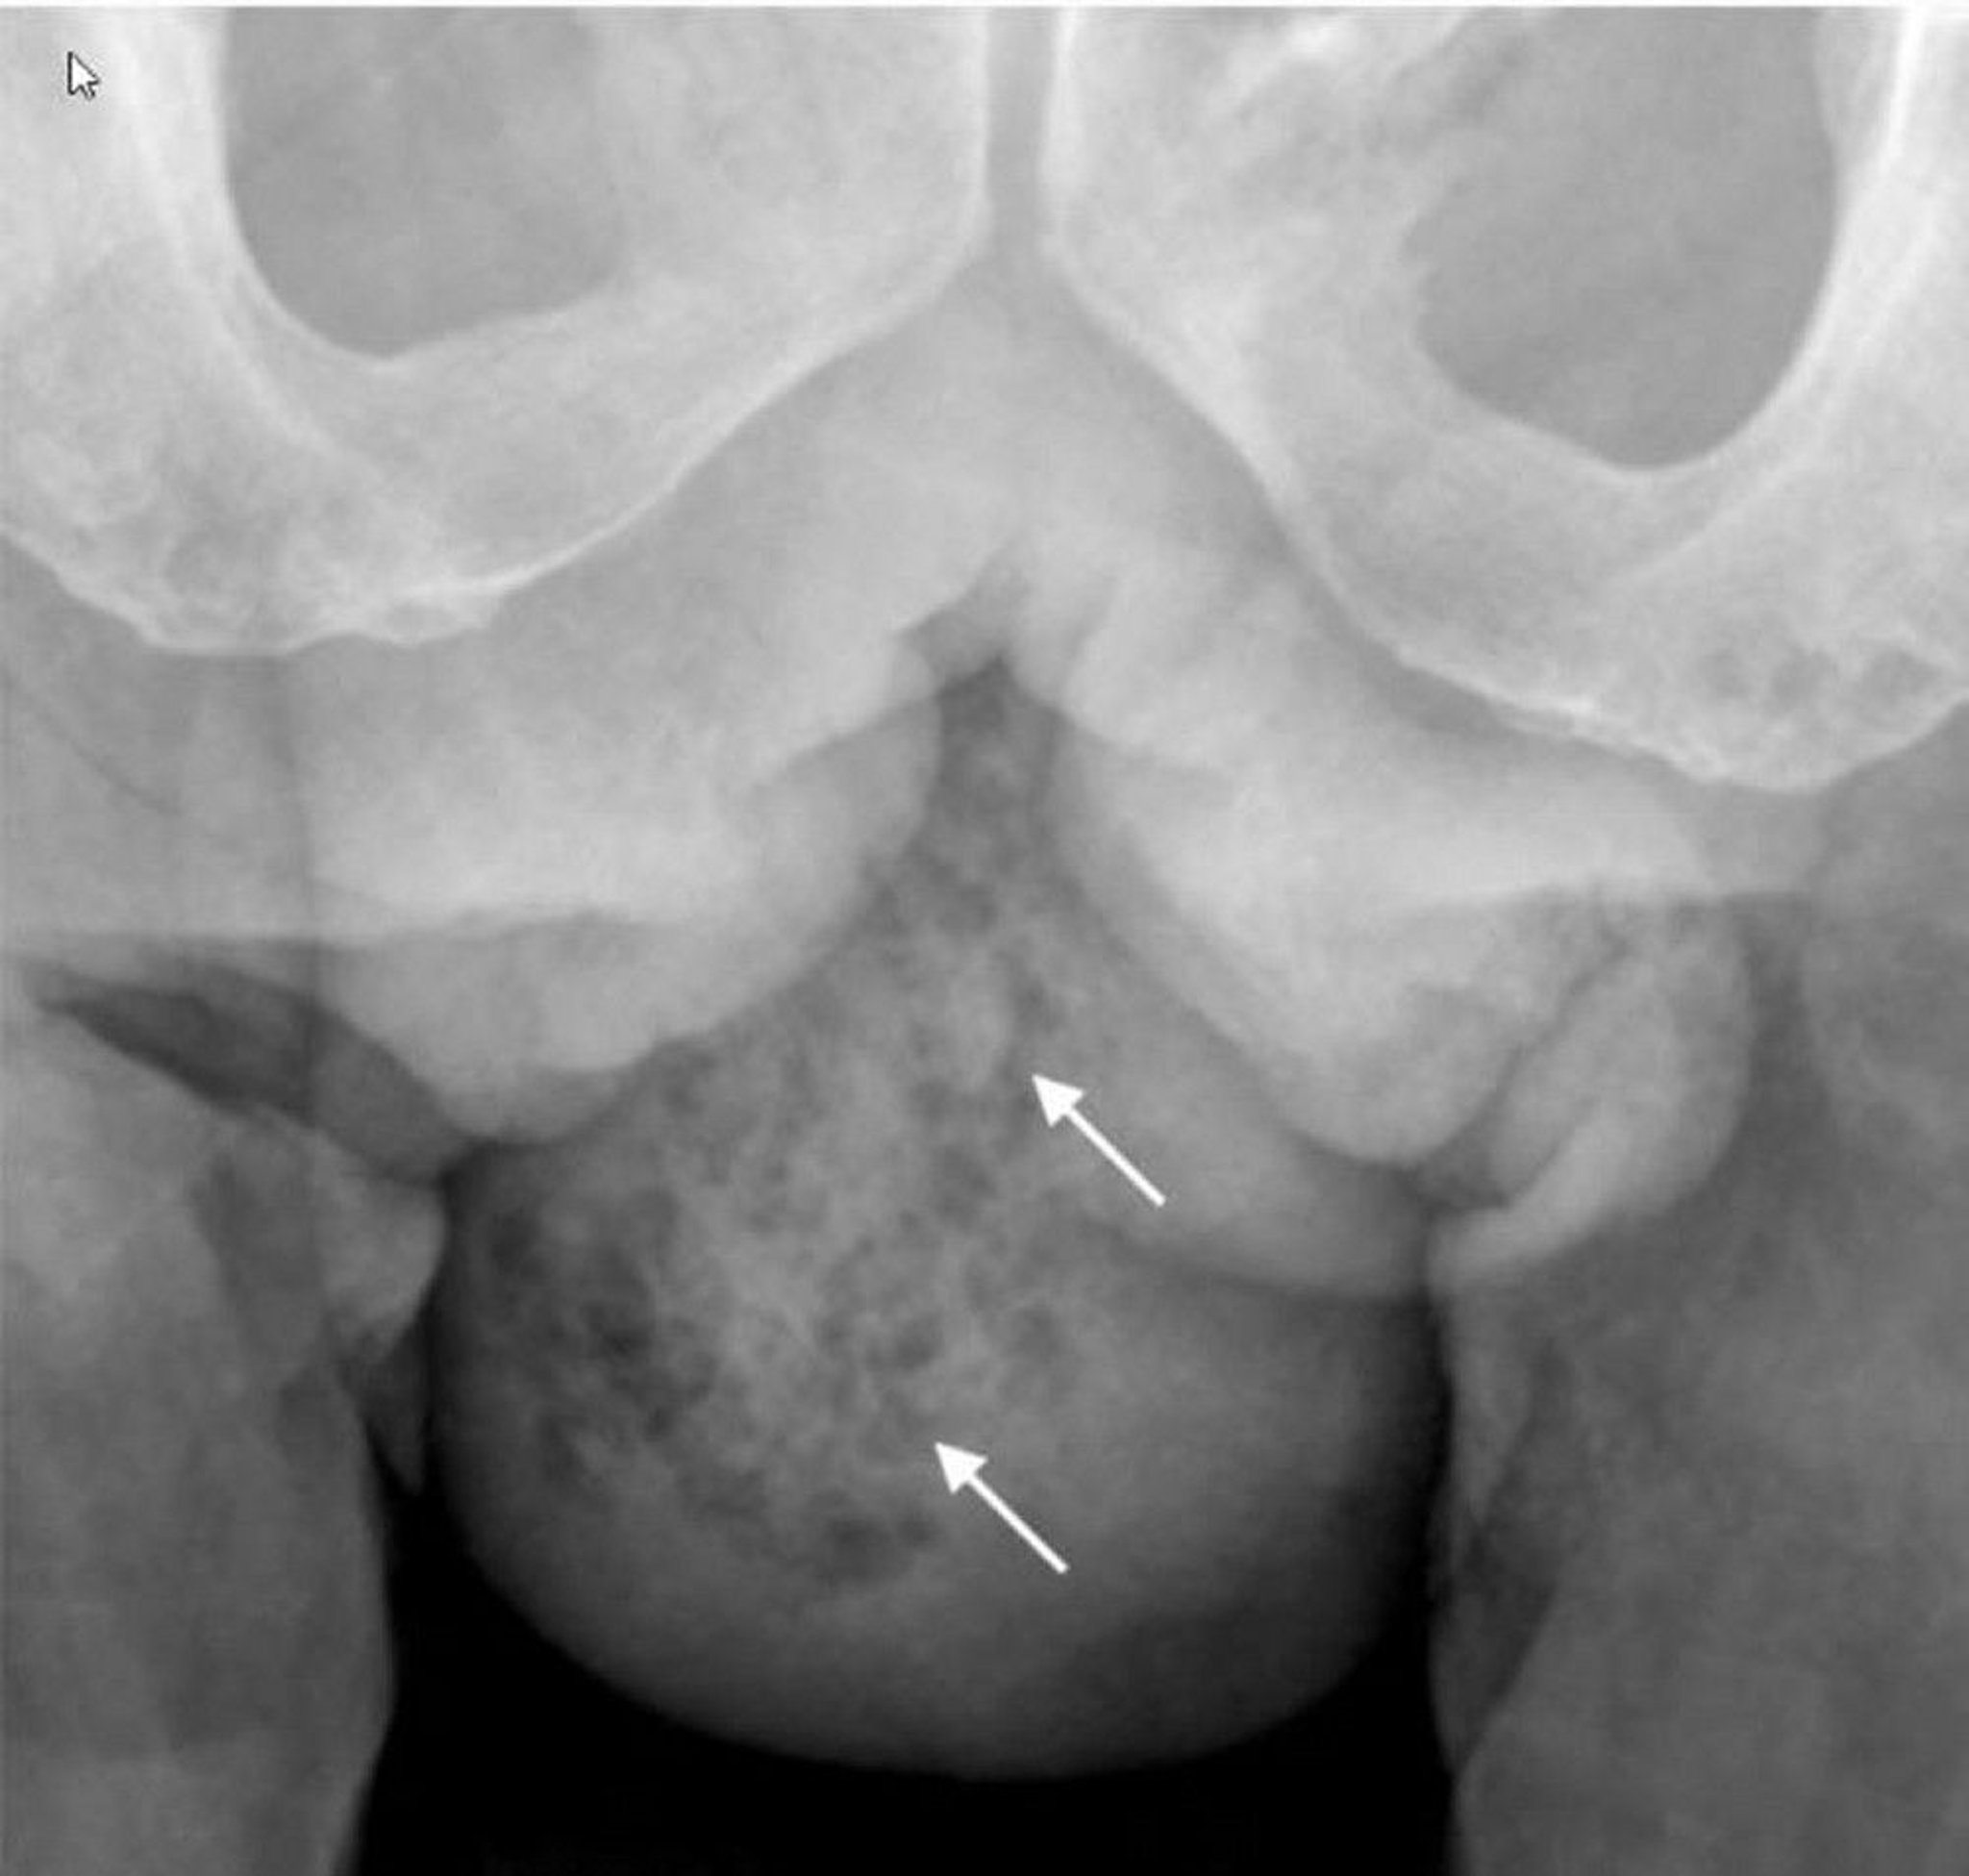

This x-ray shows soft-tissue gas in the right hemiscrotum (arrows).